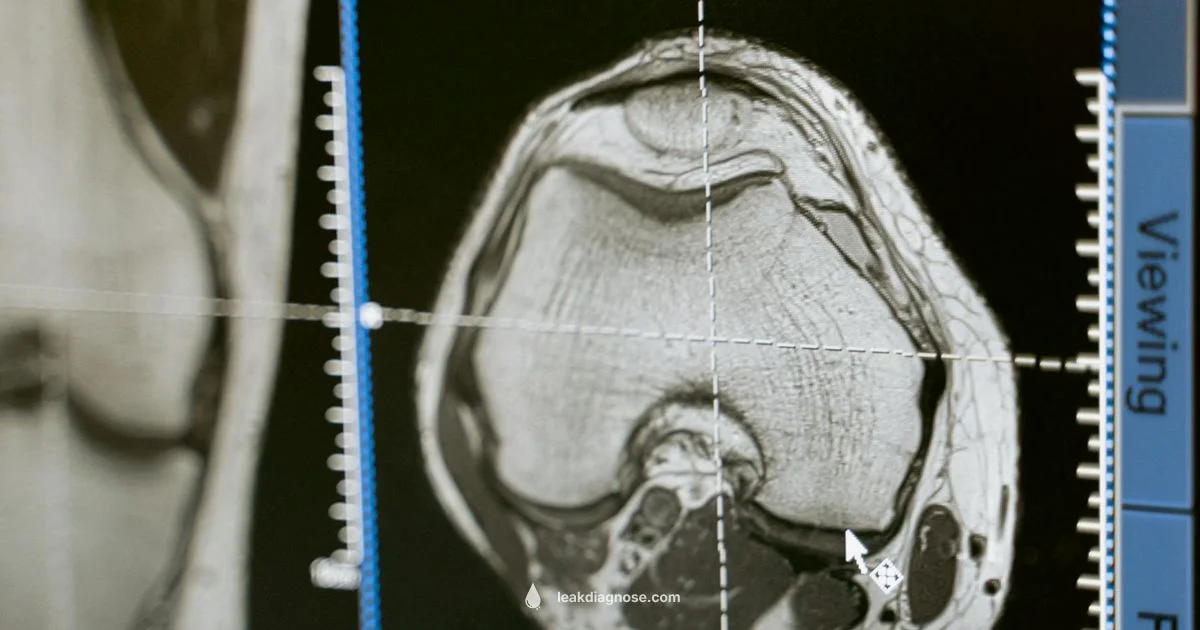

Diagnosis of an occult CSF leak relies on a combination of history, examination, and specialized tests. A key test is beta-2 transferrin, a protein found almost exclusively in CSF, which can be detected in nasal or ear discharge if present. Imaging studies such as MRI of the brain and spine or CT myelography help locate the source and assess surrounding structures. In some cases, a provocative or dynamic imaging study is used to observe CSF flow or to reproduce symptoms under controlled conditions. Because leaks without visible drainage can be hard to detect, clinicians may perform repeat testing or assign a monitoring plan. The goal is to confirm presence, identify location, and evaluate the risk of complications while guiding appropriate treatment.